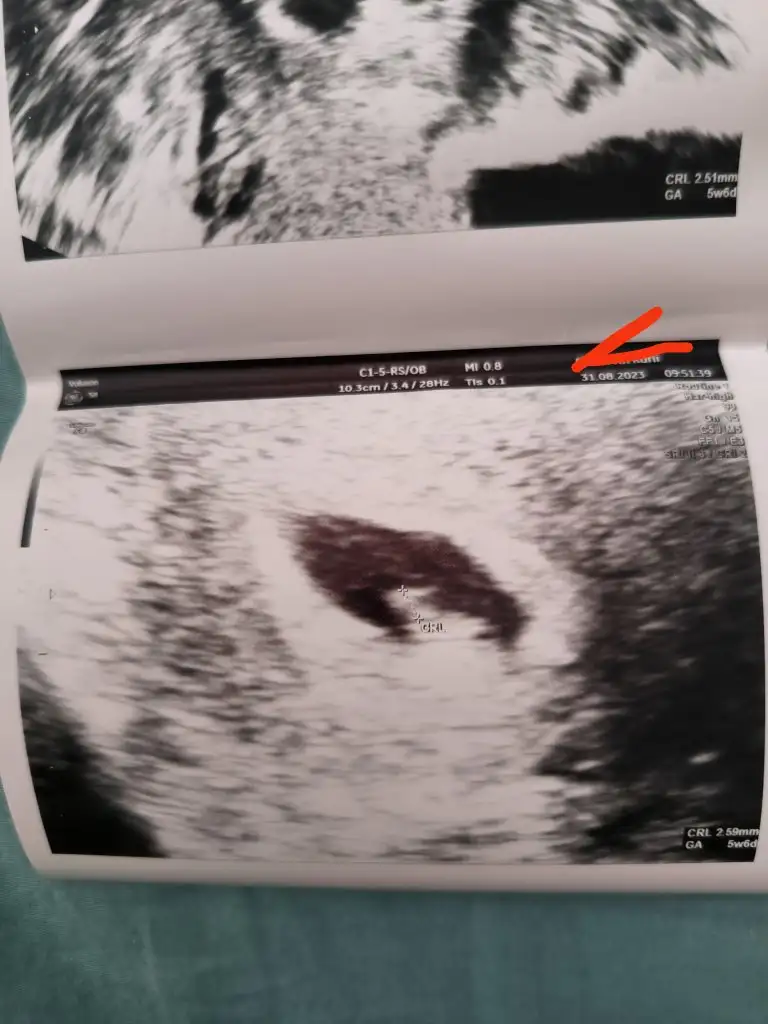

Yaaa bak gördün mü kuzum onca üzdüler seni buradaki arkadaşlara da aynı durumdan söz etmişlerdi onlar seni rahatlatmaya çalıştı çok şükür bak bebeğin orda kalp atışını duyucaksın en kısa zamanda annesine tutunmuş sağlıklı bi bebek o rabbim kucağına sağlıkla almayı nasip etsin inşallah çok sevindimKızlar ben mucize bi haberle geldim, dün biraz kahverengi akıntım olunca kesin kürtaj olacak diye bugüne eski doktorumdan özel hastaneden aldığım randevuyu iptal ettim, aşırı gerilmistim, aşırı yipranmistim ve iki gün doğru dürüst birşey yememistim, kürtaja hazırlandım, sabah 7 de hastanede olacaktık işlem icin, gece uyumadan önce Instagram'da hikayelere bakarken fenomen Özden Özdoğan var onun hikayesine denk geldim, tamamen tevafuk, bebek 6 haftalık ve kesede görünmüyordu, bikez daha soru isaretleri belirdi kafamda, eşime söyledim, baktık eski doktorumun randevulari da dolmuş, evimize yakın bi özel hastaneden Doç Dr dan randevu aldık sabah 9 15 e. Heyecanla ve korkuyla hayırlısı için dua ederek bekledim sıramı. Dr ultrasonla baktı ve bebegim görünüyordu. Kalp atışları da yeni oluşmaya başlıyor dedi. Ağlamaya başladım. Diğer Dr larin kürtaj dediğini ve aslında kürtaj için çıktığımi ağlayarak anlattım doktora. Tabi devamında ne olur bilemiyoruz dedi, duygusuzca yaklasti. Haftaya tekrar kontrole çağırdı. Devamında ne olur nasıl ilerler bilmiyorum ama eğer bebeğim sağlıkla dünyaya gelecek olursa diğer hastanedeki diğer 2 Dr için büyük vebal olacak gerçekten. Dr bana birsuru düşük önleyici ilaç ve iğne verdi, biraz fazla buldum aslında ama bilemiyorum, hem progestan 200 günde 2, hem duphaston hem de göbekten vurulan iğneden 2 tane, sadece dün kahverengi lekelenmem olmuştu ondan mı verdi acaba bunca ilacı. Sonuçta geç döllenme olduysa ondan geç görünmüştür bebek, bir de cihaz farkı tabiki, bu kadar ilaca gerek var mıydı bilemiyorum.Diger doktorların tavrını şu anda aklım hiç almıyor. Bir de bu kısmını da söylemeden geçemeyeceğim, benden tahliller istedi, gereksiz para ödemek istemediğim için sağlık ocağında yaptirsam olur mu dedim, torch (toksoplazma) sağlık ocağı yapmıyor dedi, bilmem şu şu da sağlık ocağında yanlış çıkıyor onları da isteyelim dedi mecburen yaptırdım ve muayeneyle birlikte 5000 TL civarı para ödedim. Denize düşen yılana sarılır misali oldu. Eski doktoruma gidebilseydim çok daha farklı olurdu ama her şey nasip. Bundan sonrası için de inşallah en hayırlısı en güzeli olur. Destekleriniz için hepinize tekrardan çok teşekkür ederim. Aklıma gelenleri etiketliyorum, hatırlayamadiklarim kusuruma bakmasınTweeetyy A Afratafrac edahandro melegim can Zumruduanka96 Niqu

İnşallah canım çok sağolun hepinize çok teşekkür ederim, kalp atışlarını duyamadık ama gördük, yavaştan başlamıştı yanıp sönmeye, şükürler olsunYaaa bak gördün mü kuzum onca üzdüler seni buradaki arkadaşlara da aynı durumdan söz etmişlerdi onlar seni rahatlatmaya çalıştı çok şükür bak bebeğin orda kalp atışını duyucaksın en kısa zamanda annesine tutunmuş sağlıklı bi bebek o rabbim kucağına sağlıkla almayı nasip etsin inşallah çok sevindim